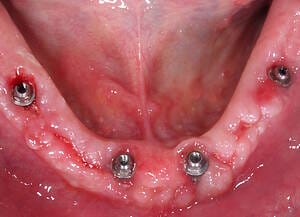

Natalie’s treatment began with a comprehensive clinical assessment, including a review of her medical and dental history, a full examination, and analysis of her functional difficulties such as her tongue habit and altered bite. A 3D cone-beam CT scan was then taken to assess bone quality and volume, identify areas of infection, and map important anatomical structures to ensure safe implant placement.

All data were transferred into digital treatment planning software, allowing virtual placement of implants and collaboration with the dental laboratory before surgery. This enabled careful evaluation of long-term outcomes and ensured the design of provisional and final prosthetics could be completed with precision. Following these discussions, the decision was made to proceed with the Fixed-Teeth-in-a-Day approach using the All-on-4 technique.

Surgical phase